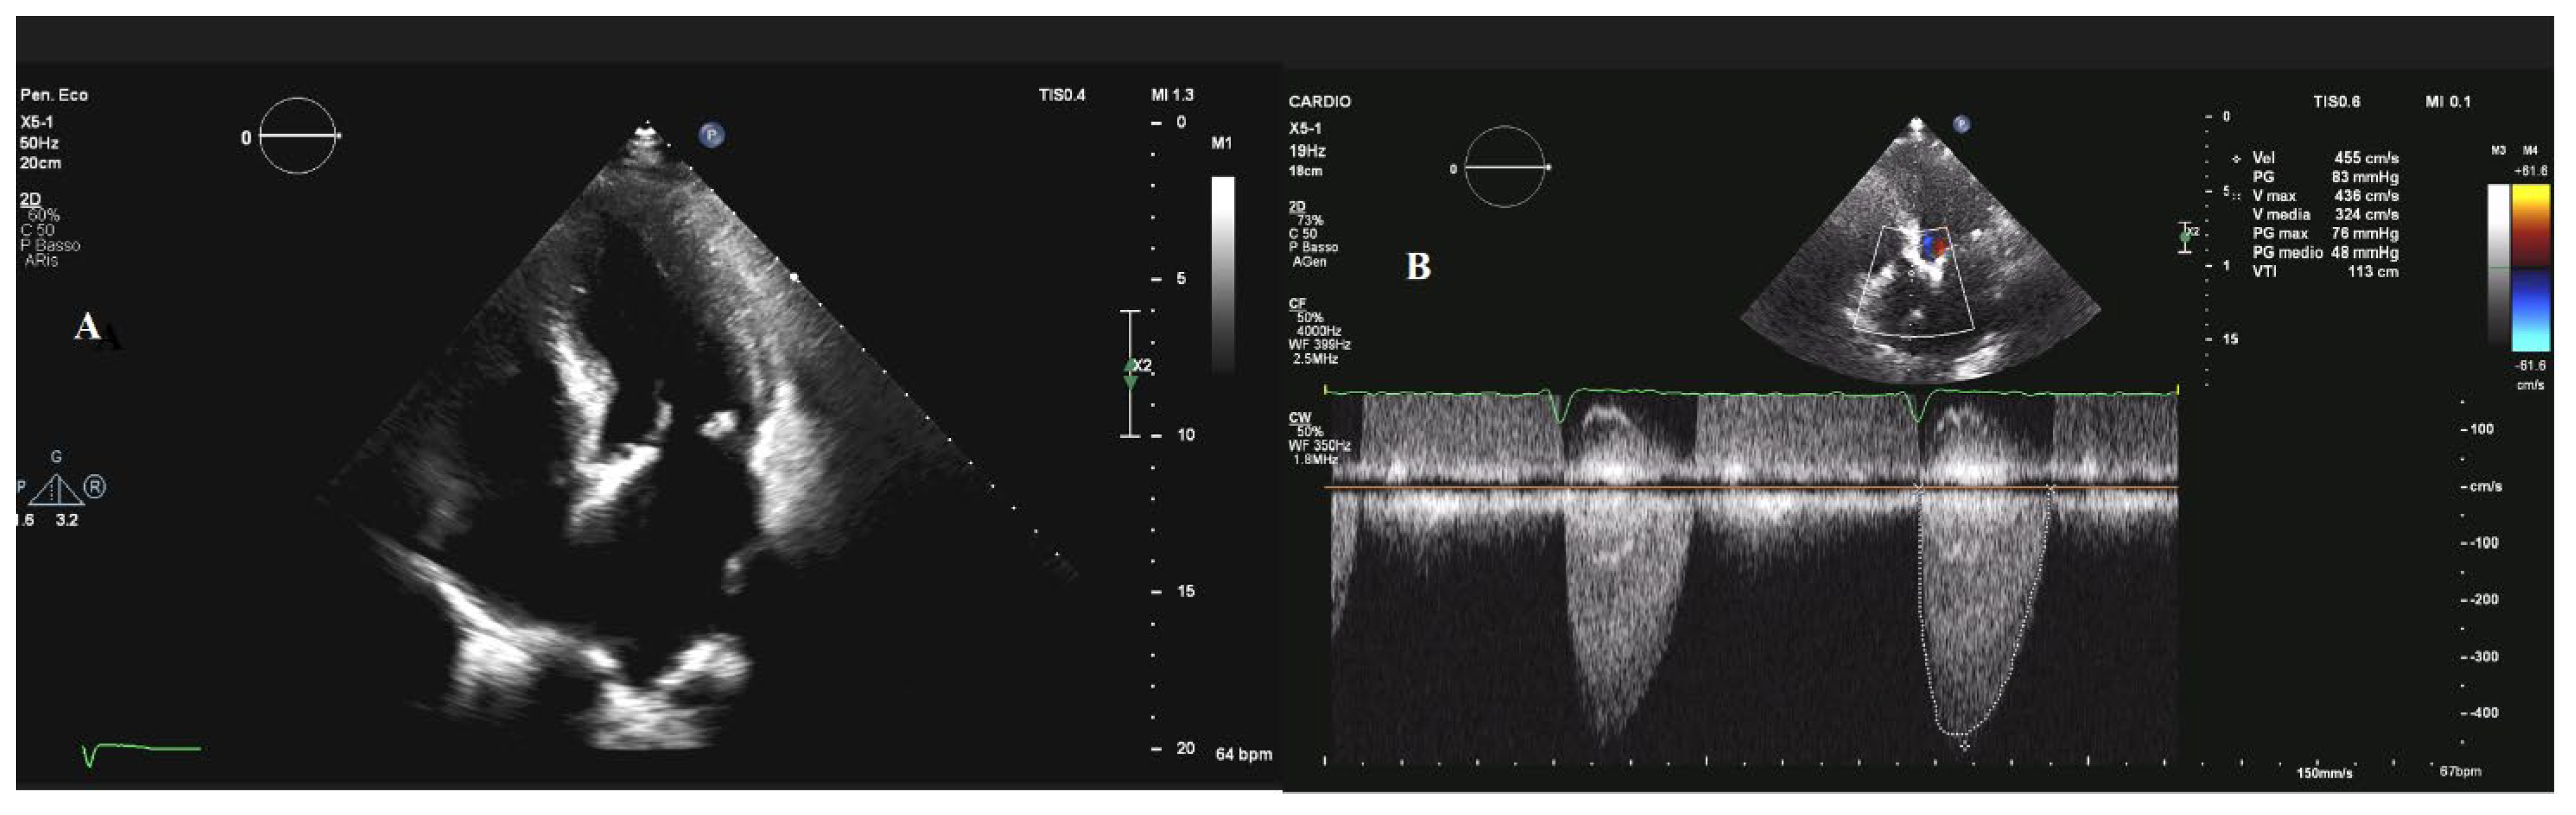

| Aortic Stenosis | Degenerative (81.9%), rheumatic (11.2%), Congenital (5.6%), post-endocarditis (1.3%) | CAVD: Aspecific Bicuspid valve: fusion between right and left leaflets is the most common Rheumatic: commissural fusion | 3.4% in the elderly | Aging, hypertension, diabetes, chronic kidney disease |

| Aortic Stenosis | Mild: every 3–5 y Moderate: every 1–2 y Severe: every 6–12 mo | N.A. | Severe AS in symptomatic patients or asymptomatic patients with LV systolic dysfunction or a positive stress test